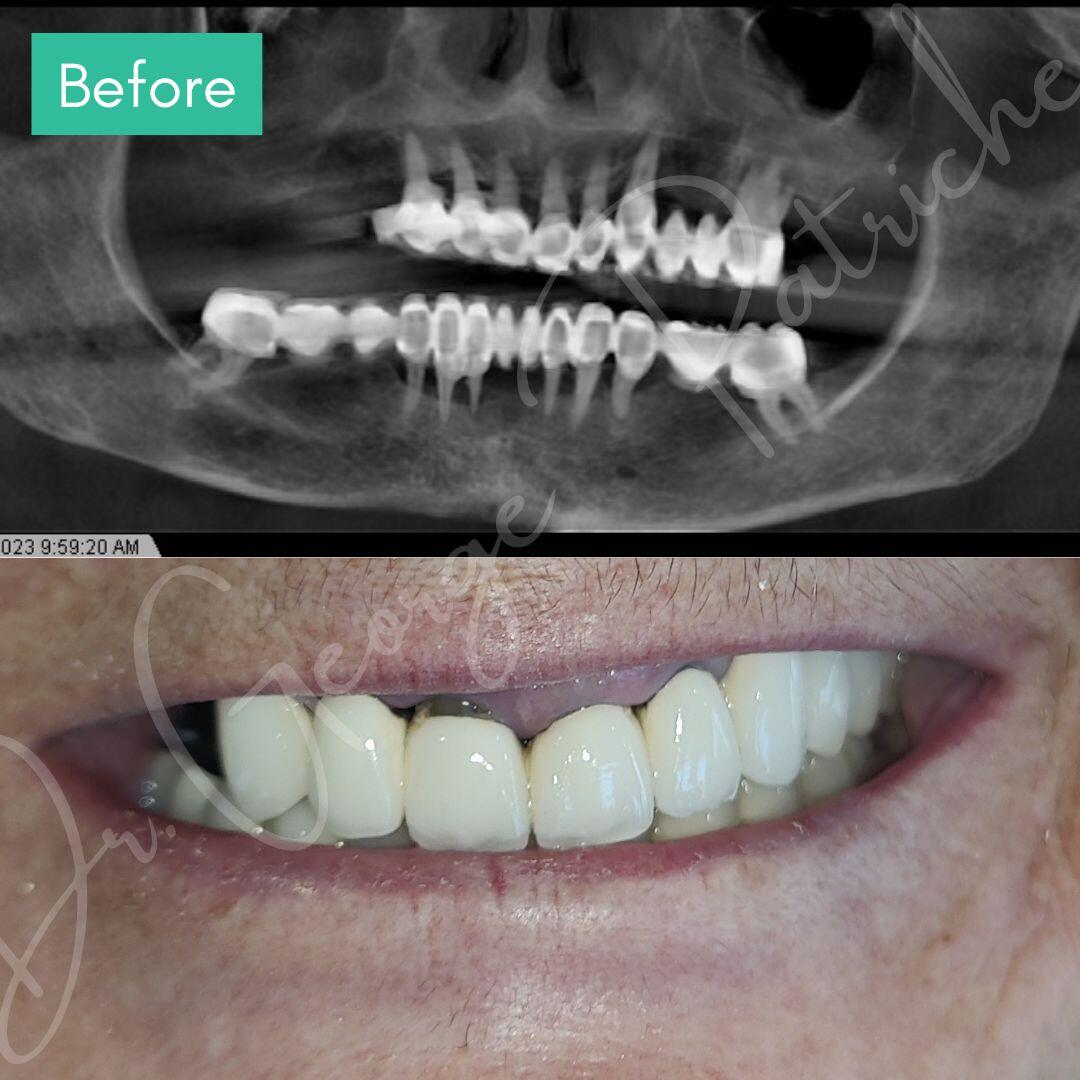

Before & After